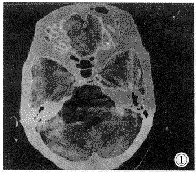

听神经瘤 桥小脑角区最常见肿瘤。本组中占80%(12/15),与文献报道基本相符。肿瘤源于前庭神经鞘膜管内部分,生长慢,常见于成人。CT表现有如下特点:①平扫多为低或低等混杂密度灶,低密度为主(7/12),边缘不清。②增强后都有明显强化,多为不均匀性强化(8/12),囊变坏死区不强化,也可呈花环状强化;强化灶边缘清楚而不规则。③骨窗见内听道口扩大(12/12),典型改变呈喇叭口状;病变以内听道口为中心;多数病例病变以窄基与岩骨相连(9/12)。④其它表现:部分病例见与肿瘤相邻桥小脑角池扩大,国外学者认为它代表肿瘤压迫脑组织,致该部分脑组织萎缩,此征象可除外脑内肿瘤(图1、2、3)。

图1、2、3 右桥小脑角听神经瘤。平扫呈低密度、强化明显、内有囊变坏死区、内听道“喇叭口”改变。